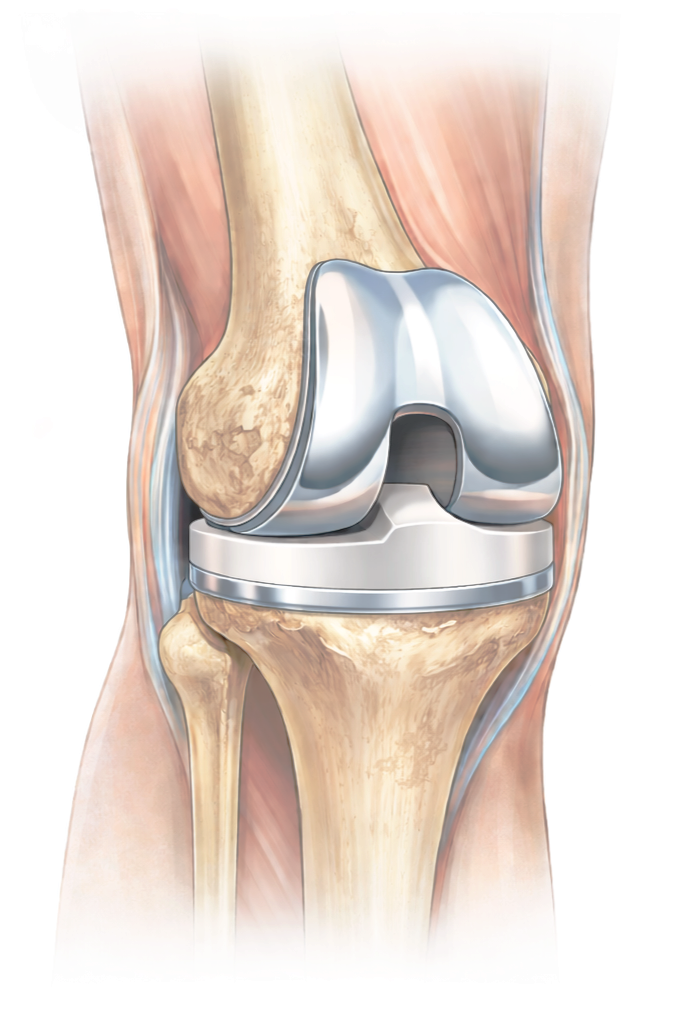

Medical illustration of knee replacement implant used to restore joint function.

Total knee replacement treats advanced knee arthritis by replacing the worn surfaces of the joint with metal and polyethylene implants.

Robotic assistance adds a layer of planning and precision. Before bone preparation begins, the knee’s alignment, cartilage wear, and ligament balance are assessed in detail. This allows implant positioning to be adjusted to optimize alignment and stability for long-term function.

The procedure is performed entirely by the surgeon, with robotic technology serving as an advanced tool to support accurate execution of the surgical plan.